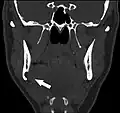

Stafne bone cavity seen on coronal CT

Stafne's defect is usually discovered by chance during routine dental radiography.[11] Radiographically, it is a well-circumscribed, monolocular, round, radiolucent defect, 1–3 cm in size, usually between the inferior alveolar nerve (IAN) and the inferior border of the posterior mandible between the molars and the angle of the jaw. It is one of the few radiolucent lesions that can occur below the IAN. The border is well corticated and it will have no effect on the surrounding structures. Computed tomography (CT) will show a shallow defect through the medial cortex of the mandible with a corticated rim and no soft tissue abnormalities, with the exception of a portion of the submandibular gland. Neoplasms, such as metastatic squamous cell carcinoma to the submandibular lymph nodes or a salivary gland tumour, could create a similar appearance but rarely have such well defined borders and can usually be palpated in the floor of the mouth or submandibular triangle of the neck as a hard mass. CT and clinical exam is typically sufficient to distinguish between this and a Stafne defect. The Stafne defect also tends to not increase in size or change in radiographic appearance over time (hence the term "static bone cyst"), and this can be used to help confirm the diagnosis.[11] Tissue biopsy is not usually indicated, but if carried out, the histopathologic appearance is usually normal salivary gland tissue. Sometimes attempted biopsy of Stafne defects reveals an empty cavity (possibly because the gland was displaced at the time of biopsy), or other contents such as blood vessels, fat, lymphoid or connective tissues. Defects of the anterior lingual mandible may require biopsy for correct diagnosis at this unusual location.[5] The radiolucent defect here may be superimposed on the lower anterior teeth and be mistaken for an odontogenic lesion. Sometimes the defect may interrupt the contour of the lower border of the mandible, and may be palpable. Sialography may be sometimes used to help demonstrate the salivary gland tissue within the bone.